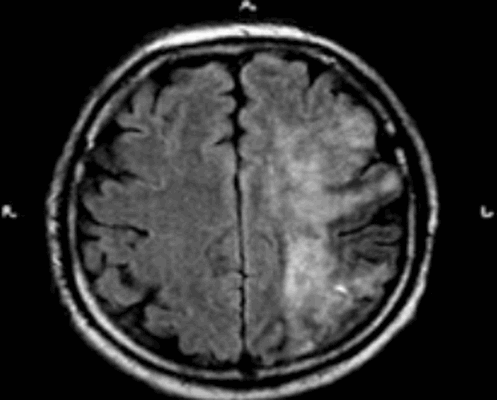

МРТ головного мозга. Т2-взвешенная аксиальная МРТ через ствол. Тонкое темное кольцо гемосидерина вокруг ствола и в мозжечке. Сидероз головного мозга.